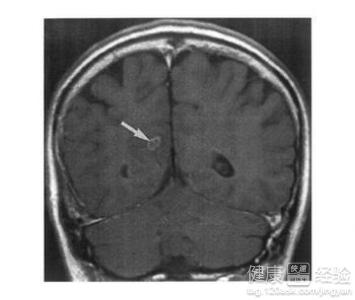

血吸蟲侵入人腦部就可能引起腦型血吸蟲病。既然是病蟲感染,那麼治療一般就以除蟲為主。大家不需要過於焦慮,綜合多年經驗,我總結出腦型血吸蟲病的一般治療方法。下面我和大家分享一下腦型血吸蟲病的治療方法。

2有明顯臨床症狀的患者可以進行開顱手術切除;對腦部炎症水腫反應,造成急性顱內壓增高,有腦脊液循環阻塞或腦疝形成而脫水劑療效不能持續或無效時,根據病情可以施行一側或雙側颞肌減壓術或腦室-腹腔引流術。但術後一般仍需內科驅蟲治療。